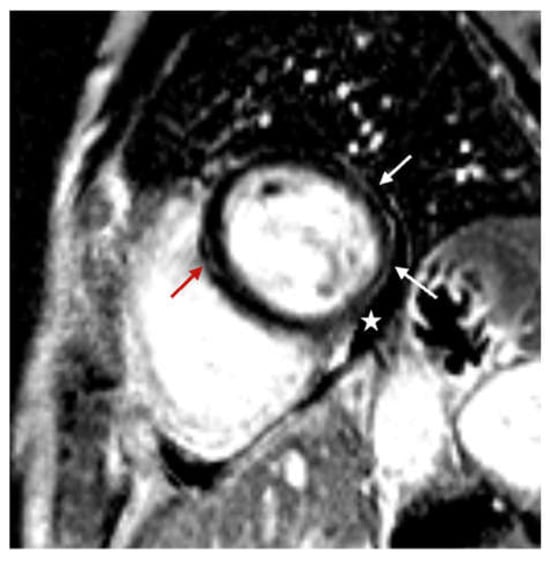

| LGE, n (%) | 67 (78.8) |

| Distribution of LGE, n (%) | |

| Subepicardial | 27 (31.8) |

| Mid-wall | 7 (8.2) |

| Transmural | 1 (1.2) |

| Subepicardial and mid-wall | 32 (37.6) |

| Late pericardial enhancement, n (%) | 34 (40.0) |

| Pericardial effusion, n (%) | 44 (51.8) |